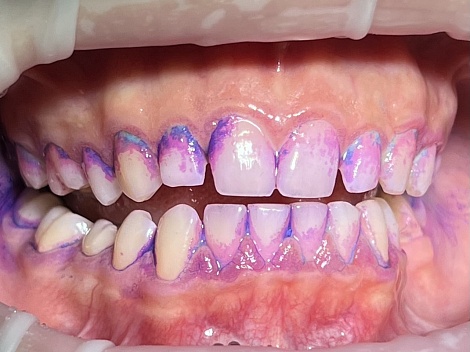

Комплексная профессиональная гигиена полости рта и реминерализация эмали

До

После

Услуги:

Гигиена зубов и полости рта ,

Чистка зубов

Заболевания:

Стоматология

«Все свои!» м.Люблино